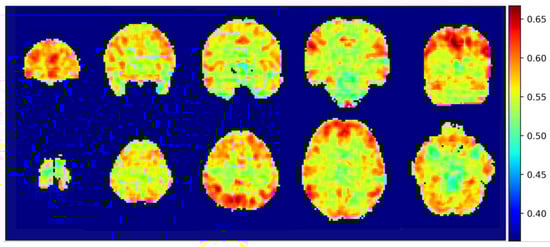

2.5. Visualization through an Integrated Gradients Algorithm

3.3. Integrated Gradients Results